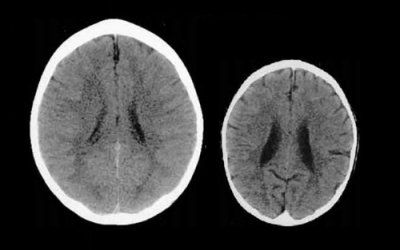

Chúng ta đều biết, bạo hành thể chất sẽ ảnh hưởng tiêu cực đến trẻ em, nhưng mới đây, các nhà khoa học Mỹ chỉ ra, bạo hành về mặt tinh thần cũng gây ra hệ quả tương tự, đặc...